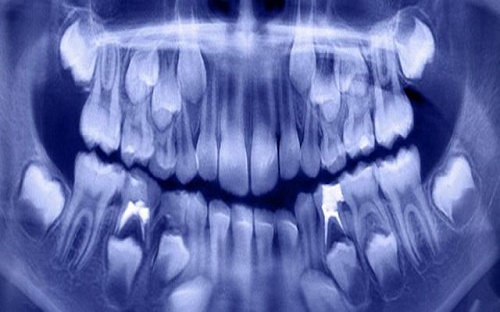

Sau khi tiến hành chụp X-quang và CT, các bác sĩ đã phát hiện khoang miệng cậu cấu trúc như một chiếc túi chứa đầy răng.

Các bác sĩ đã mất tới 5 giờ để loại bỏ hết 526 chiếc răng khỏi miệng cậu bé.

"Răng có kích thước khác nhau, dao động trong khoảng 0,1 mm đến 15 mm. Chúng trông giống như những viên ngọc trai trong một con hàu. Ngay cả những mảnh nhỏ nhất cũng có một lớp tráng men như một chiếc răng”, các bác sĩ cho biết.